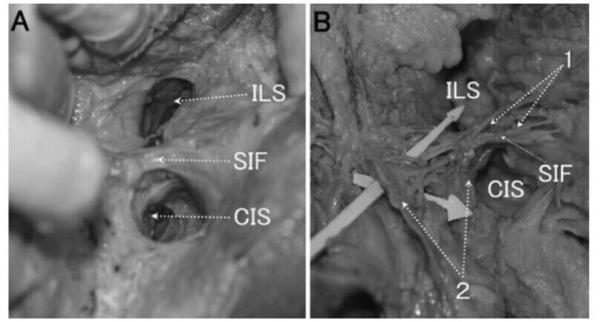

——新坐骨直肠窝学说——几个解剖概念

坐骨直肠窝隔膜(SIF

临床坐骨直肠窝间隙(CIS

肛提肌下间隙(ILS

本手术的重点:1、切开6点的外括约肌深部,确保高位肌间隙和肛后深间隙的引流。2、肛外切口必须切开坐骨直肠窝隔膜(SIF),确保坐骨直肠窝上提肌下间隙的引流。3、电刀和置管确保高位的引流和防止低位切口的过早愈合。4、刮匙对高位坐骨直肠窝上提肌下间隙的搔刮也非常重要。

很多人包括本人,一开始对这个学说没有引起重视,固执的认为坐骨直肠窝在手术中实实在在的摸得着,哪有什么坐骨直肠窝的提肌下间隙?但临床中就是可以见到持续性胀痛明显,甚至发热,皮色稍微发红或正常,一侧或两侧臀部压痛明显,切开后找不到脓腔,或稀里糊涂放出了脓液,也不知道脓液是从哪里来的。我认为这里的新解剖概念需要纠正或修改,把肛提肌下间隙(ILS)改为坐骨直肠窝提肌下间隙,把坐骨直肠窝提肌下间隙和后深间隙(PDF)一块称之为广义的肛提肌下间隙更为合适。因为后深间隙(PDF)也是提肌下间隙,单独的把ILS称为肛提肌下间隙总觉有点不妥。(图片资料由天津市人民医院李会晨博士提供,在此表示衷心感谢!)